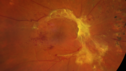

PDR and tractional macular detachment

pdr-TRD2_kesel_071719__26.png

43 files, last one added on Oct 29, 2020

Album viewed 359 times